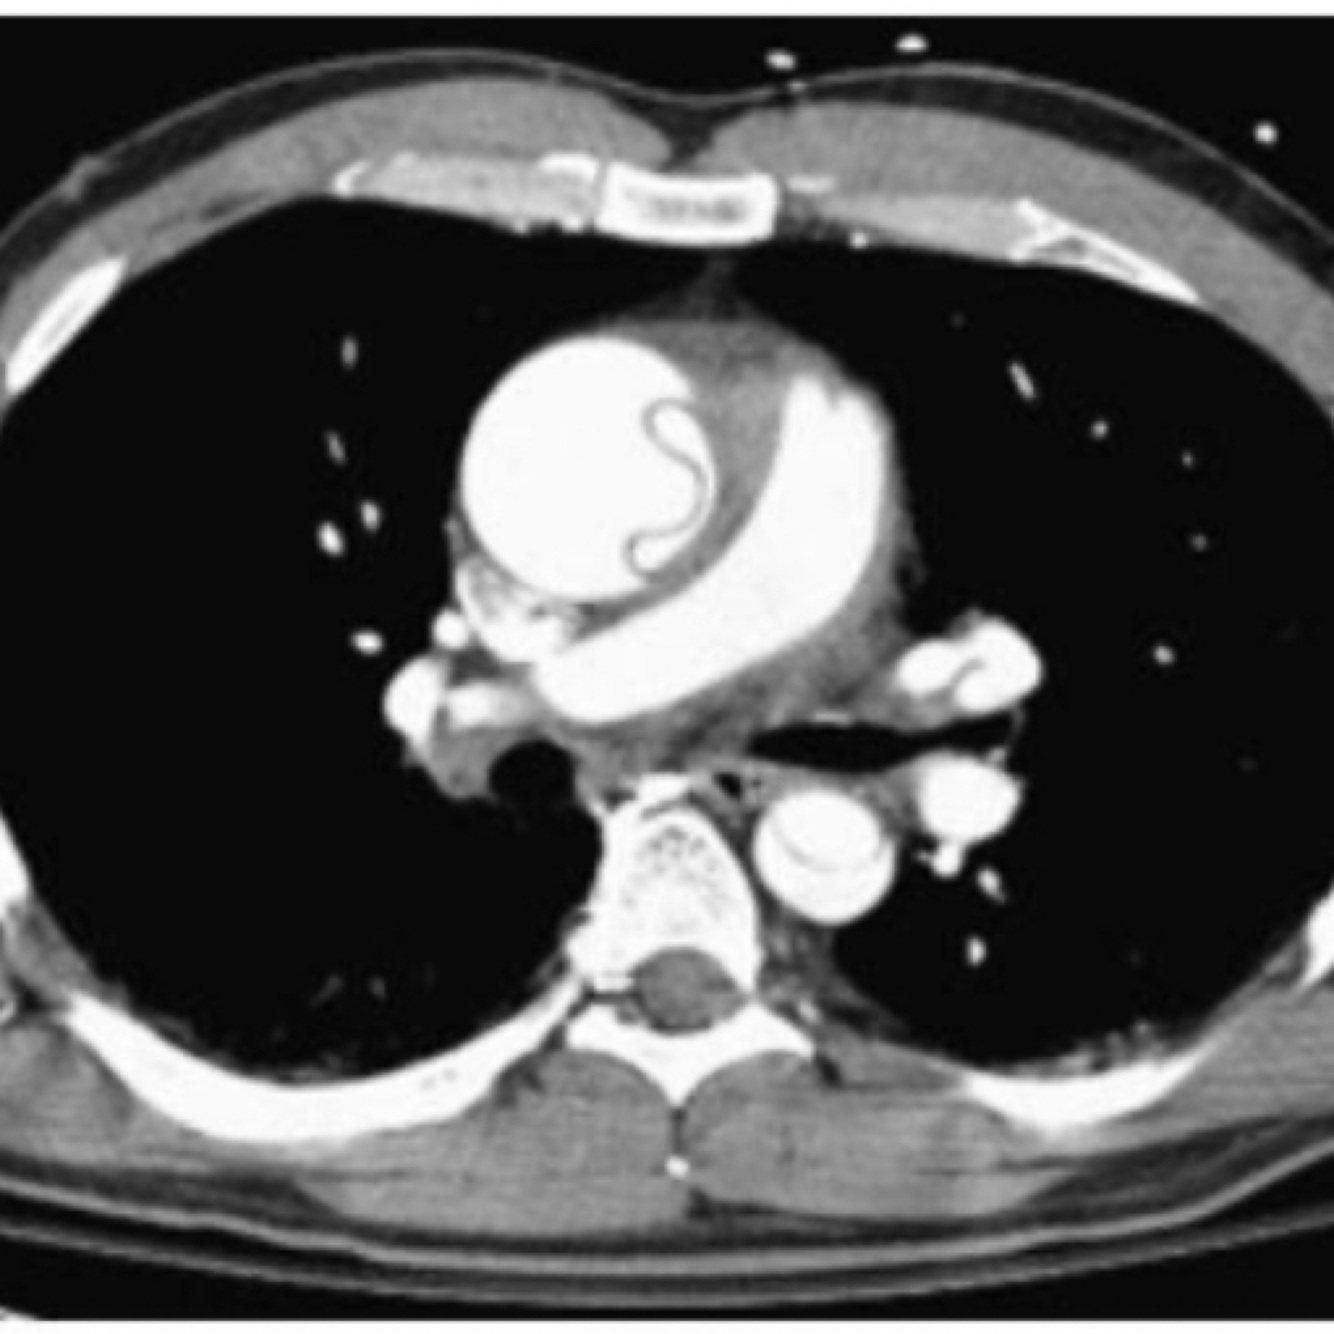

Q

Diagnóstico

A

Dissecção aórtica A